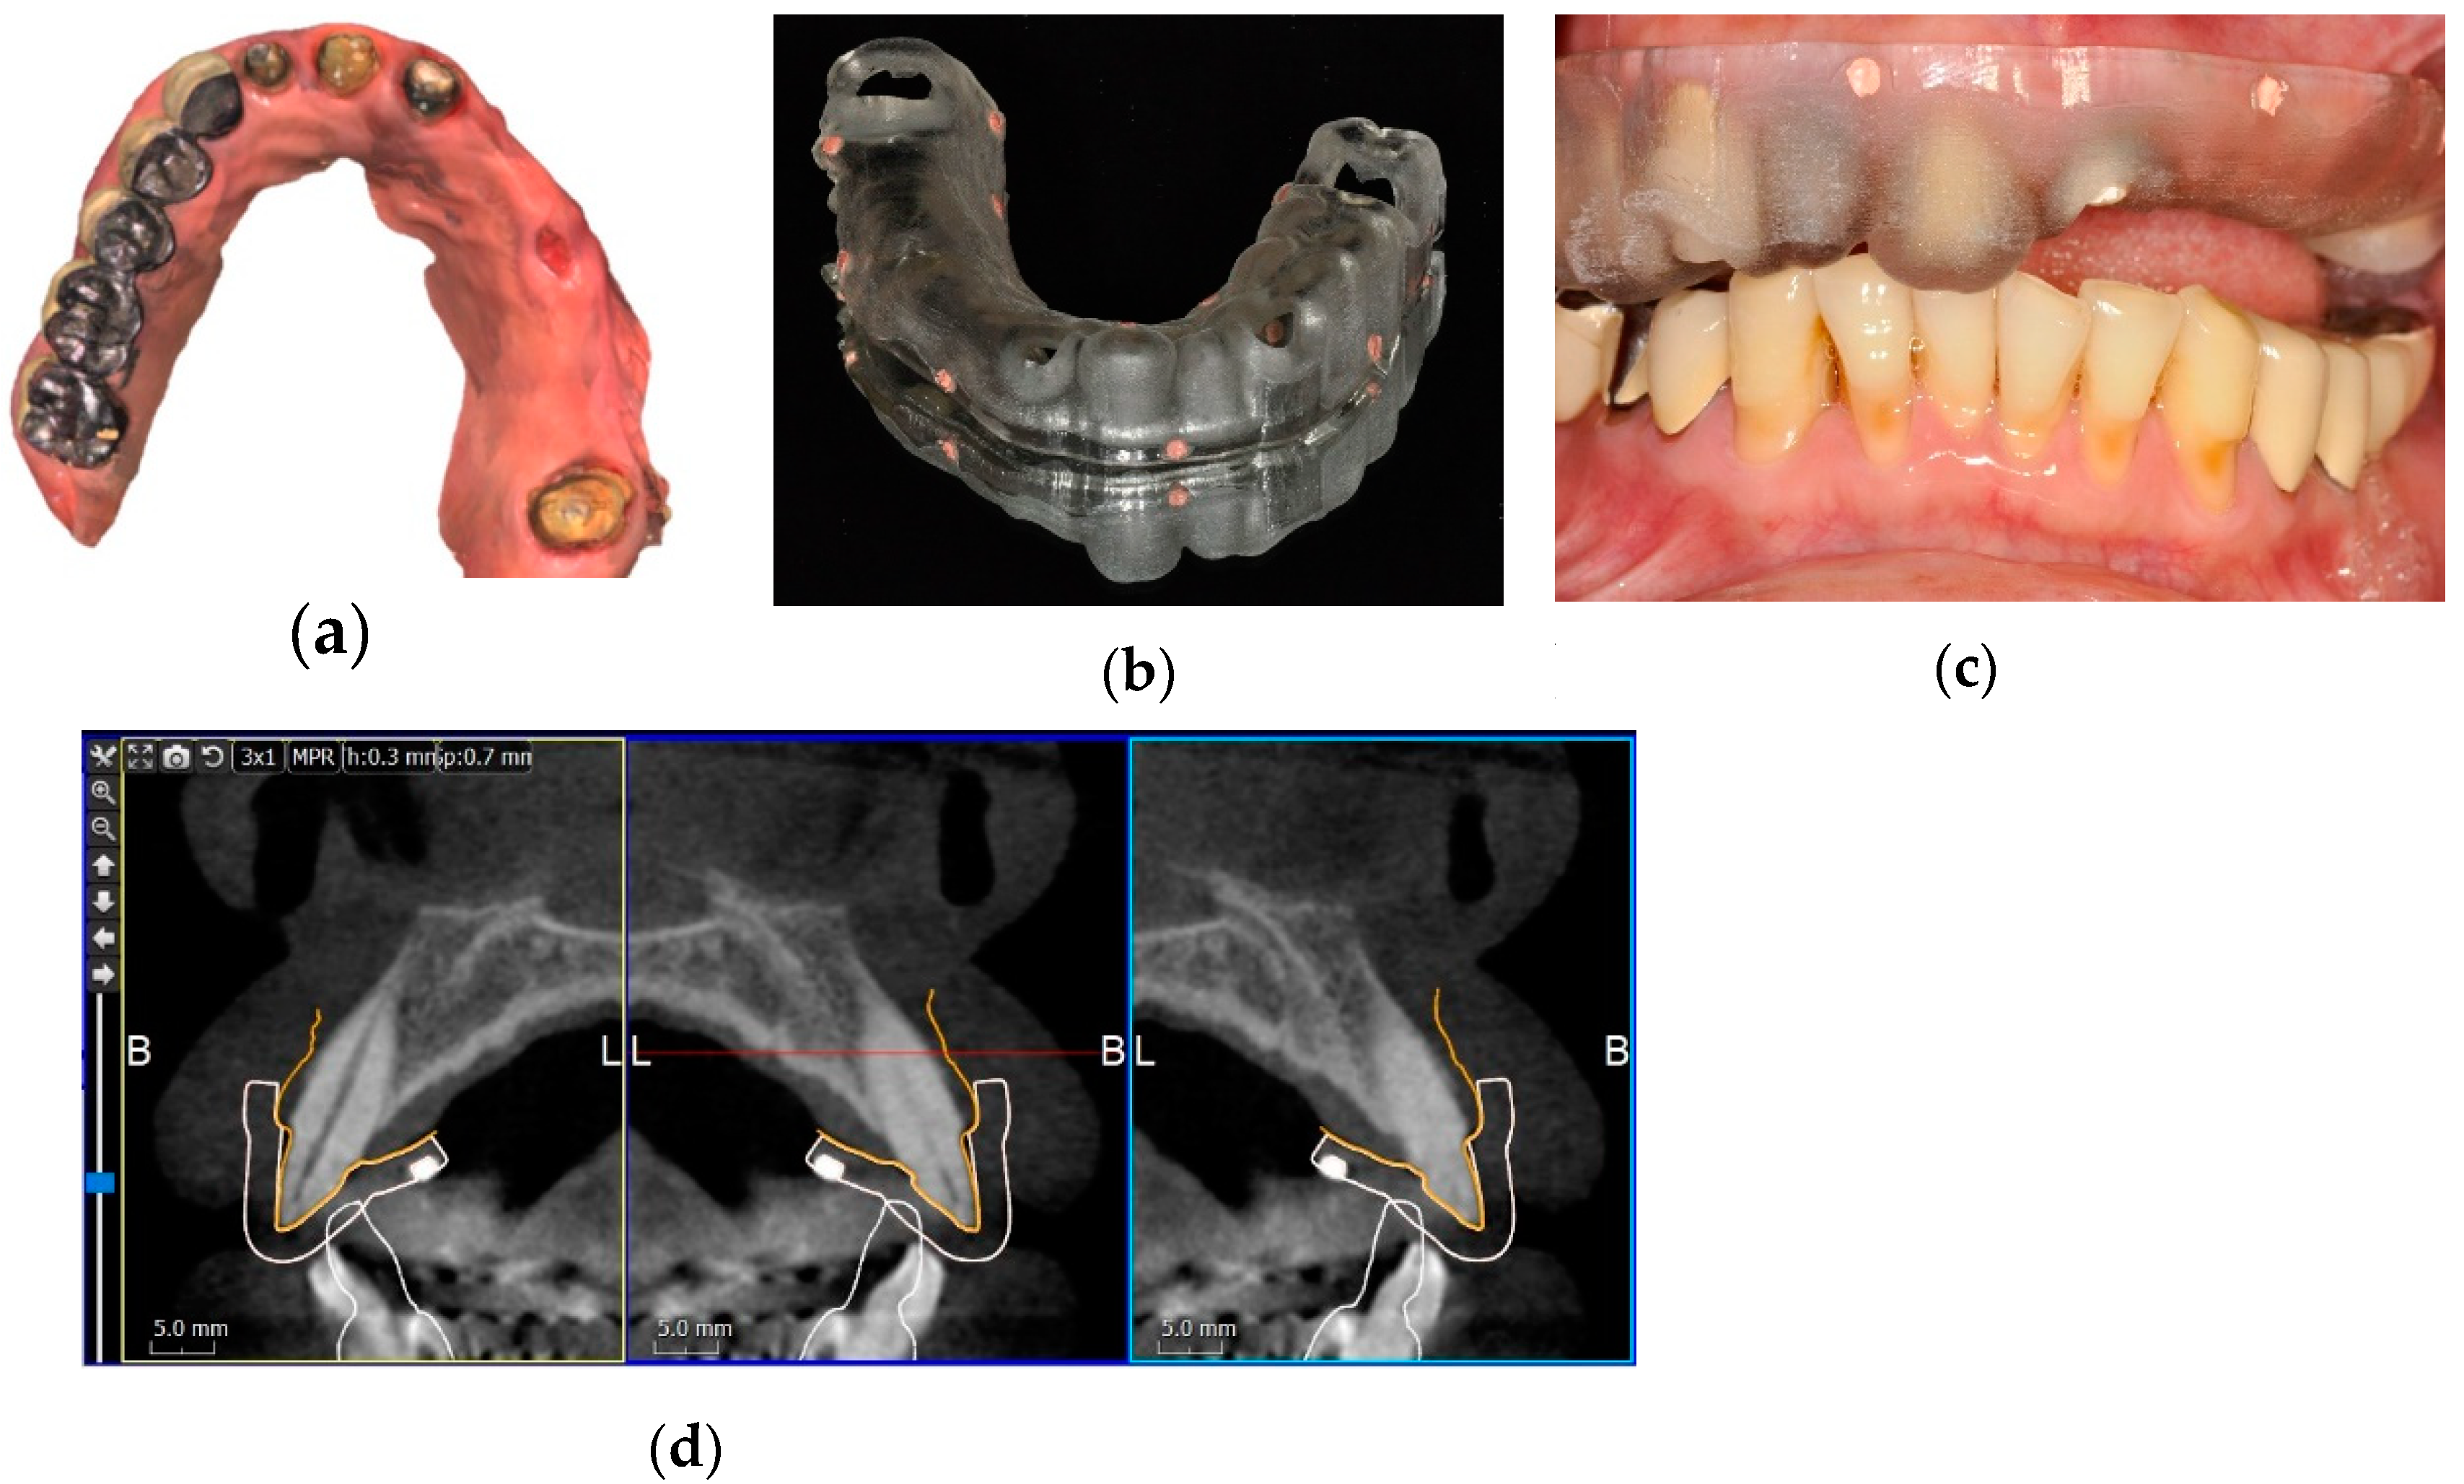

2.2. Alignment of CBCT Scan and Intraoral Scan

2.2.1. Surface Registration Protocol

2.2.2. Fiducial Marker Registration Protocol

2.3. Implant Planning and Surgical Guide Fabrication